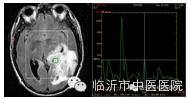

在脑肿瘤术前诊断,术前评估肿瘤特征,指导术者及术后评测肿瘤切除效果等方面有着广泛的临床应用价值。

磁共振波谱是分子成像技术,主要用于癫痫、肿瘤及梗塞的诊断与鉴别诊断。